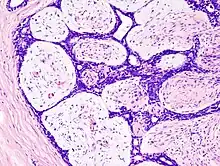

Fibroadenoma of the breast is a benign tumor composed of a biplastic proliferation of both stromal and epithelial components.[14][15] This biplasia can be arranged in two growth patterns: pericanalicular (stromal proliferation around epithelial structures) and intracanalicular (stromal proliferation compressing the epithelial structures into slit-like spaces).

These tumors characteristically display hypovascular stroma compared to malignant neoplasms.[16][17][11] Furthermore, the epithelial proliferation appears in a single terminal ductal unit and describes duct-like spaces surrounded by a fibroblastic stroma. The basement membrane is intact.[18]

Histopathologic image of breast fibroadenoma. Core needle biopsy. Hematoxylin & eosin stain. -